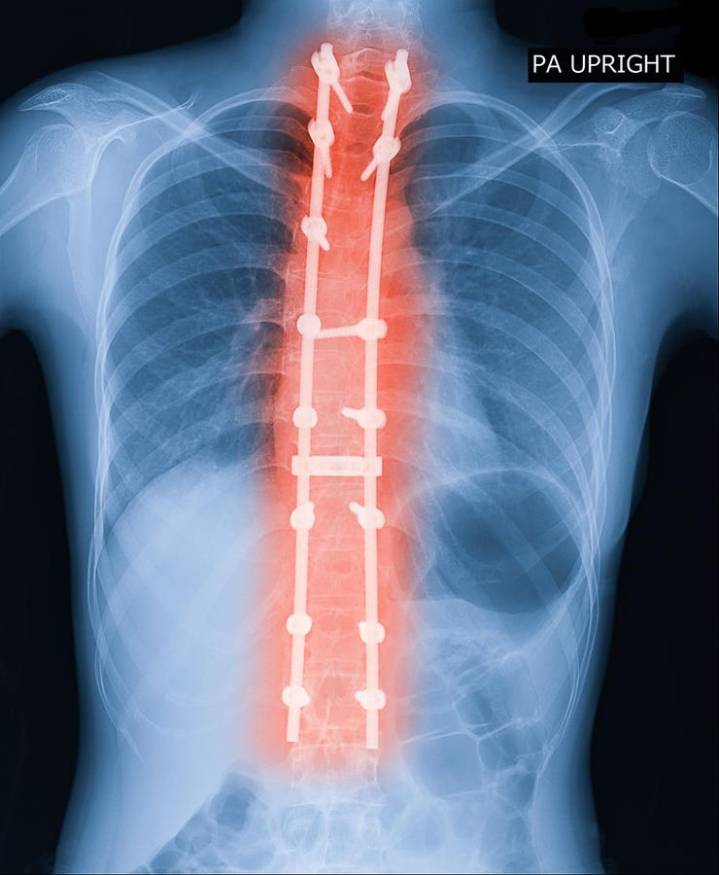

X-ray image of adult patient spine showing scoliosis surgery. Scoliosis surgeries are effective but expensive. getty

Scoliosis can cause substantial pain and functional impairment, yet the surgical interventions designed to correct it remain highly invasive and financially burdensome. This longitudinal study followed adult patients with scoliosis—defined by a lateral curvature of the spine—over an eight-year period.